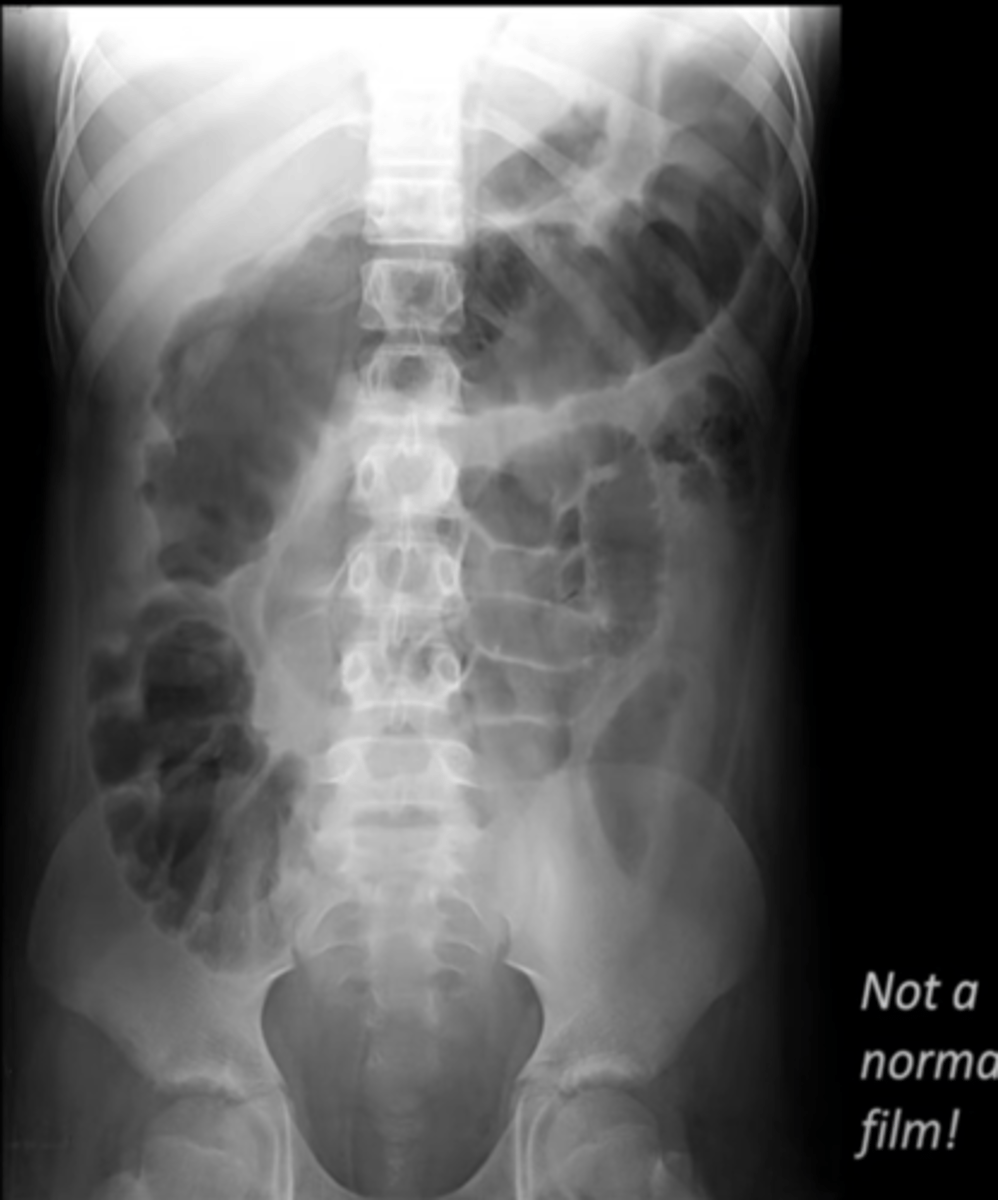

upright view of the abdomen

What view is this image in?